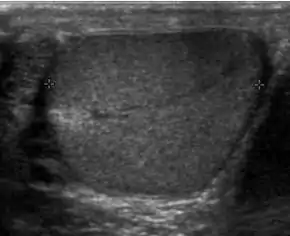

The normal adult testis is an ovoid structure measuring 3 cm in anterior-posterior dimension, 2–4 cm in width, and 3–5 cm in length. The weight of each testis normally ranges from 12.5 to 19 g. Both the sizes and weights of the testes normally decrease with age. At ultrasound, the normal testis has a homogeneous, medium-level, granular echotexture. The testicle is surrounded by a dense white fibrous capsule, the tunica albuginea, which is often not visualized in the absence of intrascrotal fluid. However, the tunica is often seen as an echogenic structure where it invaginates into the testis to form the mediastinum testis. In the testis, the seminiferous tubules converge to form the rete testes, which is located in the mediastinum testis. The rete testis connects to the epididymal head via the efferent ductules. The epididymis is located posterolateral to the testis and measures 6–7 cm in length. At sonography, the epididymis is normally iso- or slightly hyperechoic to the normal testis and its echo texture may be coarser. The head is the largest and most easily identified portion of the epididymis. It is located superolateral to the upper pole of the testicle and is often seen on paramedian views of the testis. The normal epididymal body and tail are smaller and more variable in position.